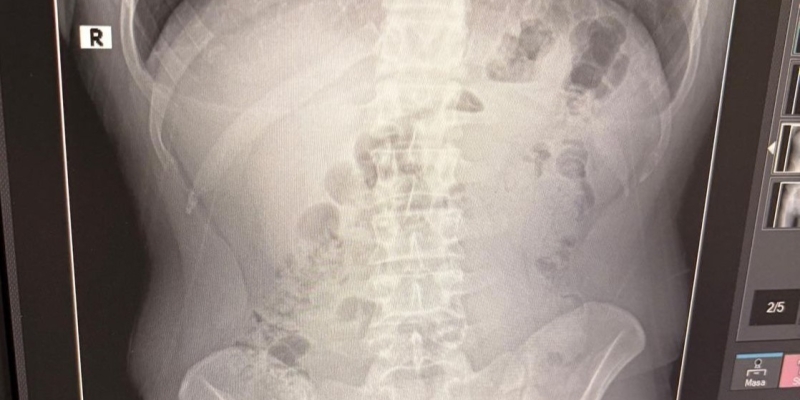

Adreste yapılan arama sırasında ekipler, şüphelilerden birinin üstünde 1 adet kapsül ele geçirdi. Şüphe üzerine tüm şüpheliler hastaneye götürüldü ve yapılan röntgen kontrollerinde 3 kişinin midelerinde kapsül içine gizlenmiş metamfetamin tespit edildi.